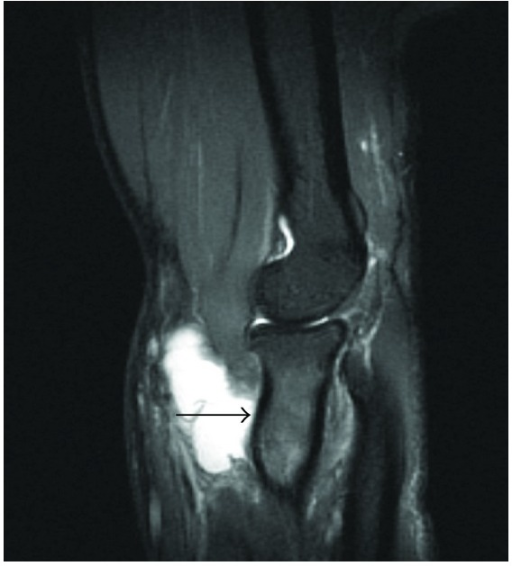

Clinical image for Distal Biceps Tendon Rupture

What imaging is used for distal biceps injuries? What are the indications for operative treatment?